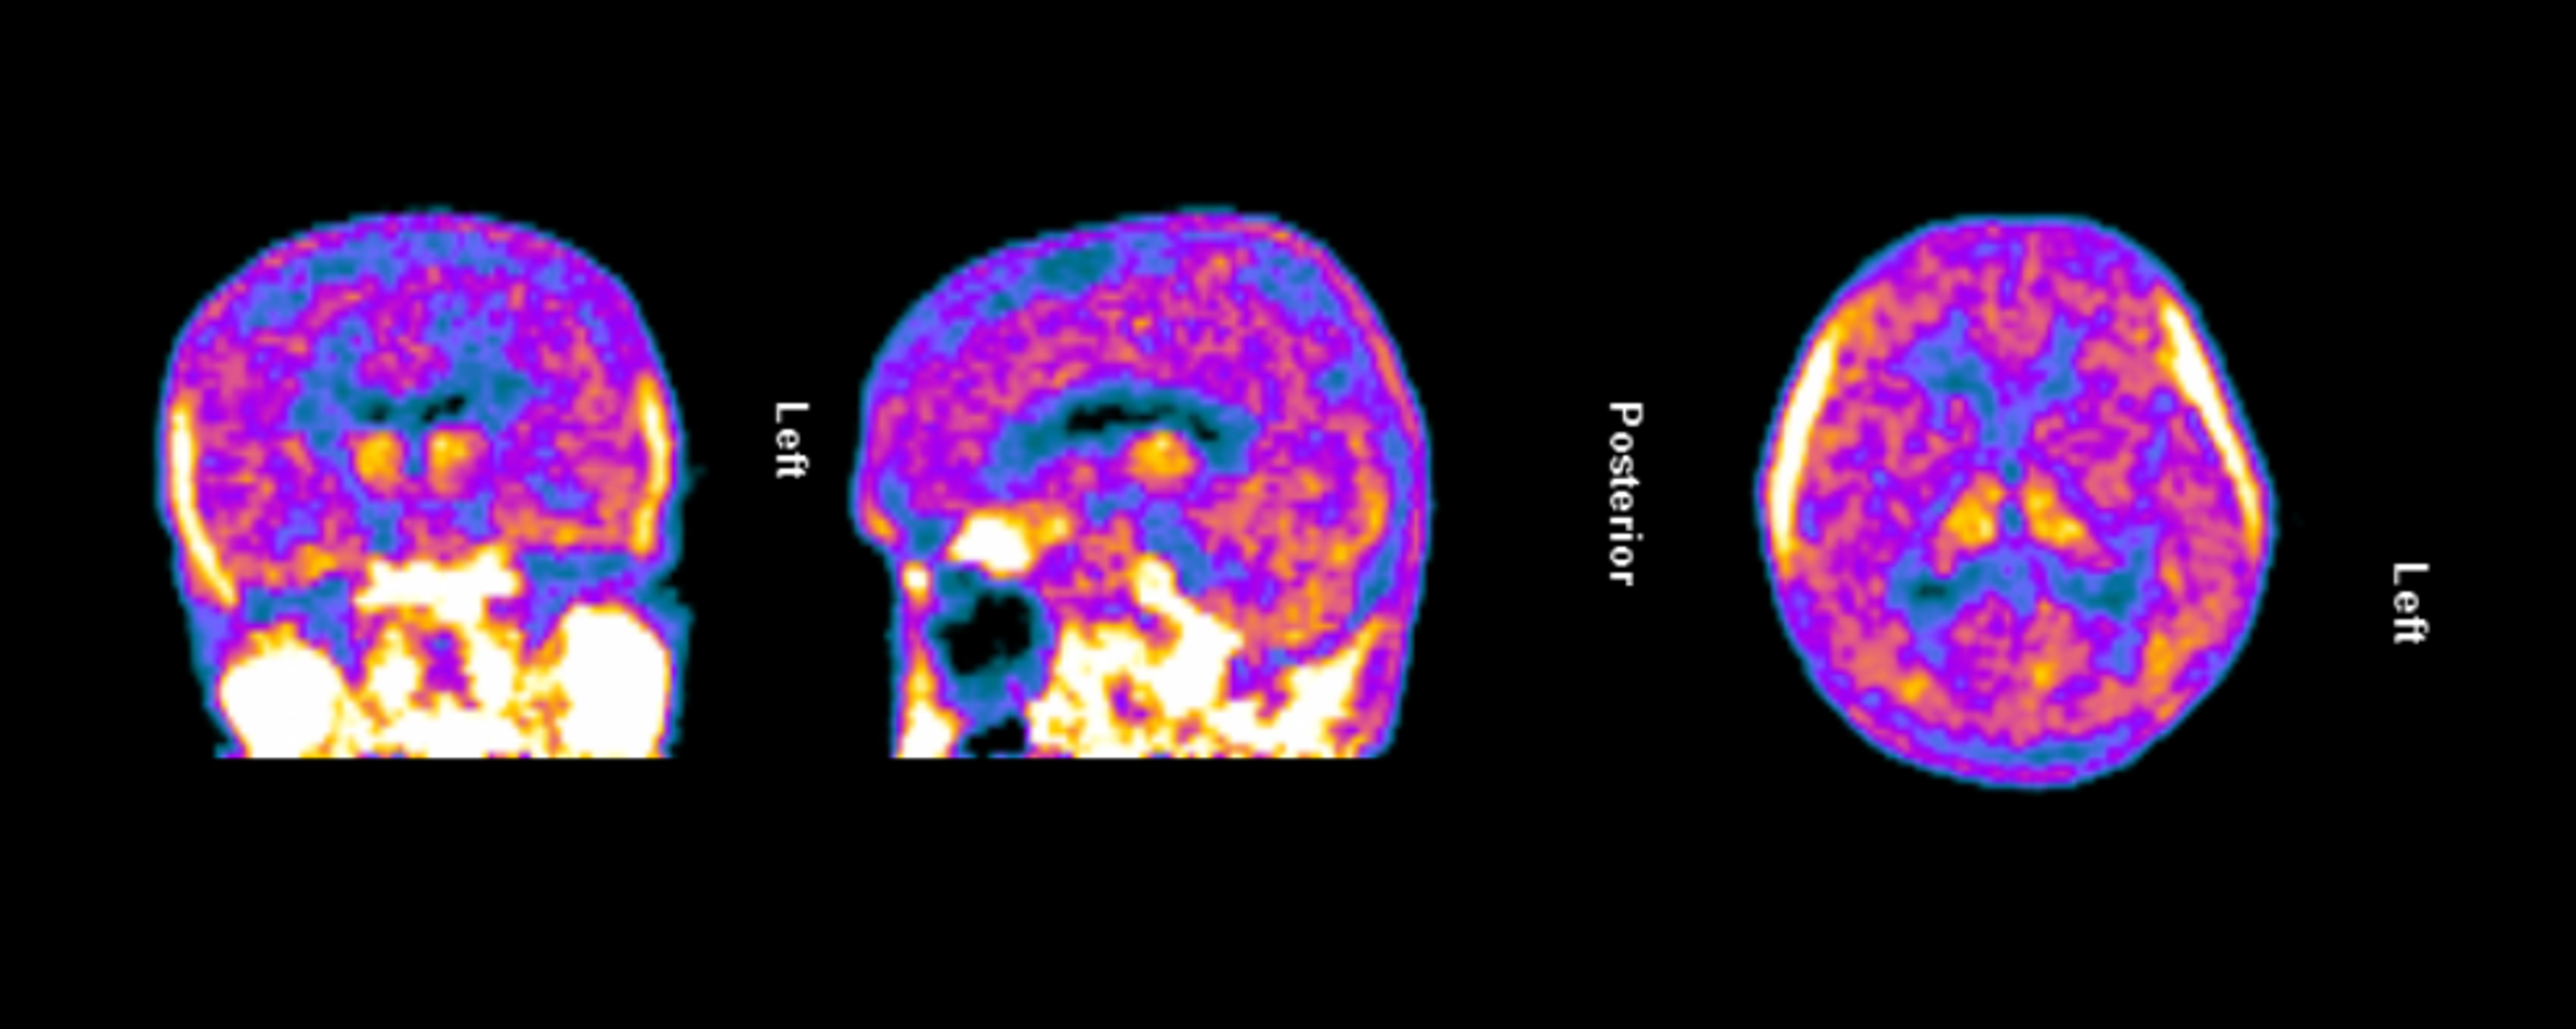

The clinical trial launch is supported by new TSPO-PET imaging evidence demonstrating persistent and widespread microglial activation in an Alzheimer’s patient despite treatment with lecanemab, confirming that neuroinflammation remains present even after amyloid plaque reduction. Lecanemab, marketed by Eisai and Biogen as Leqembi®, is one of the two FDA-approved anti-amyloid therapies for treating early Alzheimer’s and is proven to reduce beta-amyloid plaques.

Figure 1. TSPO-PET scan of an Alzheimer’s patient treated with lecanemab demonstrating persistent and widespread microglial activation throughout the brain.

Dr. Howard Weiner, Chairman of Tiziana’s Scientific Advisory Board and co-director of the Ann Romney Center for Neurologic Diseases at Brigham and Women’s Hospital, a founding member of Mass General Brigham, stated, “This PET finding is a critical insight: clearing amyloid does not turn off the brain’s inflammatory response. We believe intranasal foralumab directly addresses this residual neuroinflammation by inducing regulatory T cells to migrate to the brain and calm activated microglia — a mechanism we have already shown reduces microglial activation in secondary progressive multiple sclerosis.”

Figure 1

TSPO-PET scan of an Alzheimer’s patient treated with lecanemab demonstrating persistent and widespread microglial activation throughout the brain.